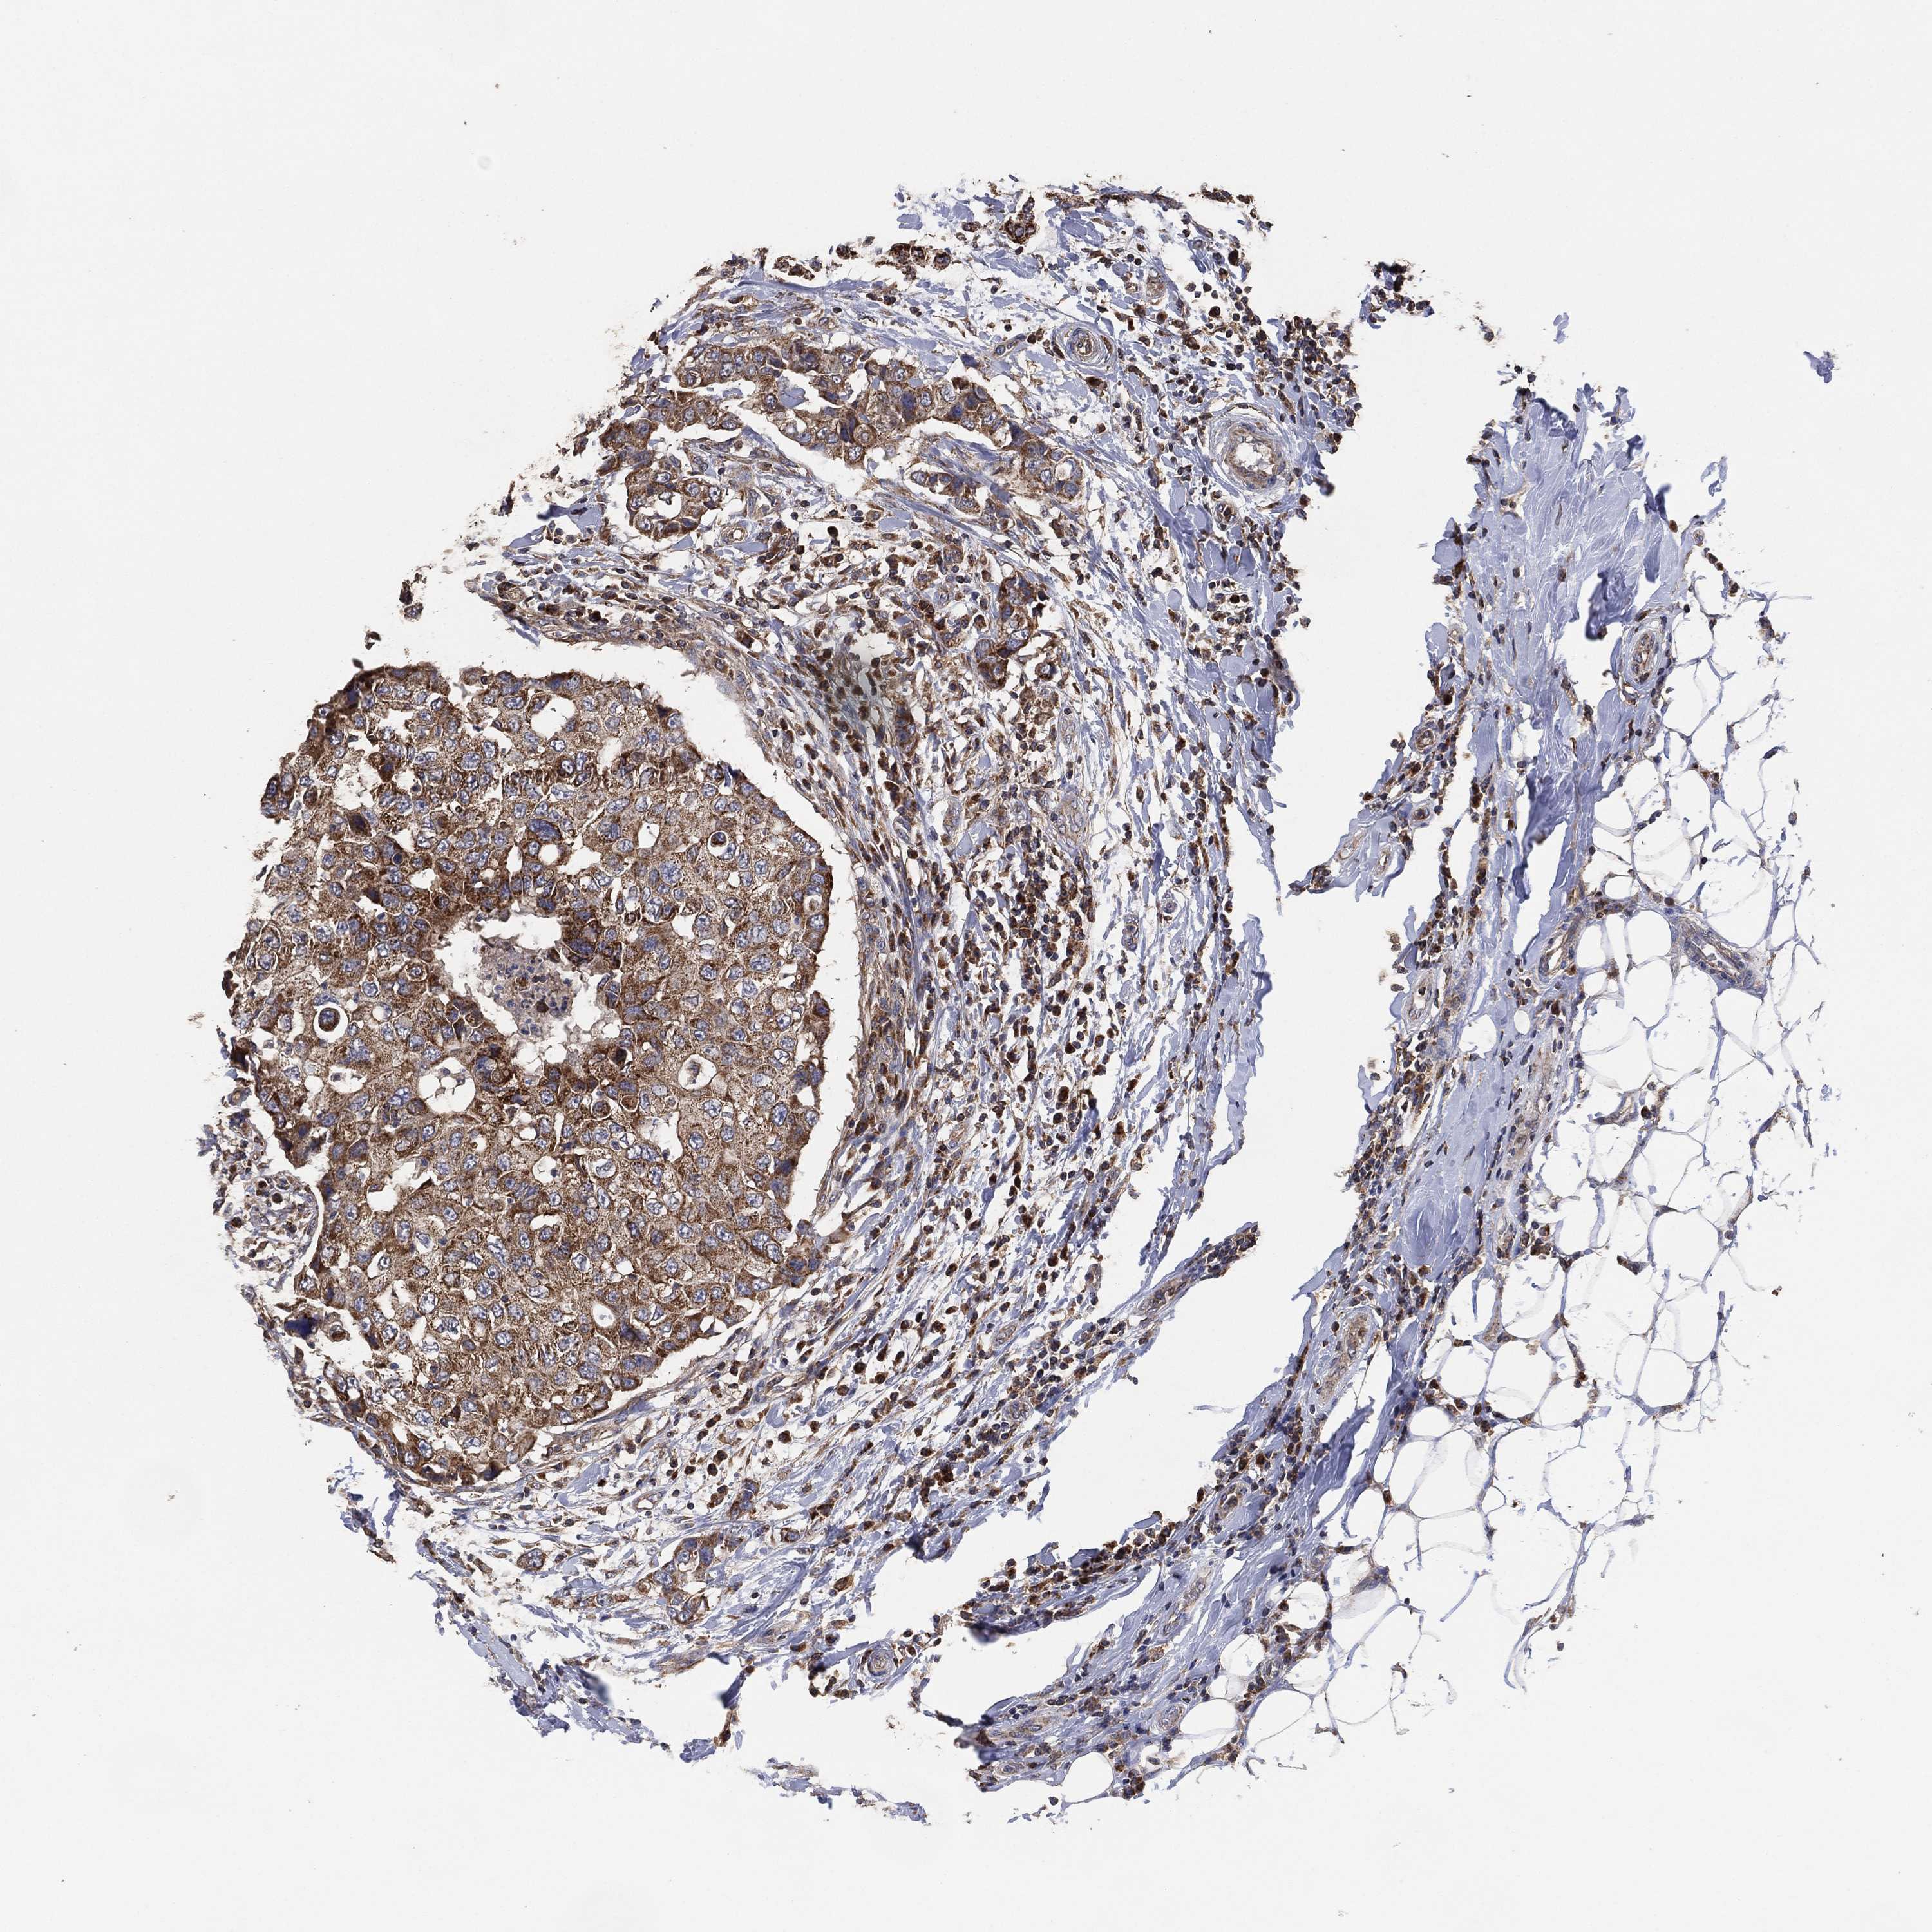

CANCER BREAST CANCER Show tissue menu

BRCA TCGA BRCA VALIDATION PROTEIN EXPRESSION